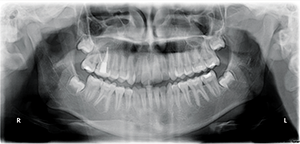

CBCT analysis revealed limited alveolar boundaries on the buccal and lingual of the mandibular anterior teeth (Fig. 3).

Fig. 3 Fig. 4

The location of the roots of the maxillary right dentition closely proximate the buccal and palatal cortical plates of the alveolar processes, which were thin particularly at the canine and first premolar with thicker cortex regions lateral to the second premolar and first molar (Figs. 4-7).